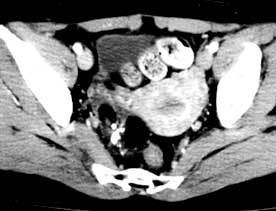

病例編號26,18歲。因卵巢未成熟畸胎瘤做手術3次。第1次:1982年4月在外院行單側卵巢腫瘤切除病檢為未成熟畸胎瘤,病理為3級。手術後8個月發現上腹腫物及大量腹水,患者極度消瘦肝γ照相見肝區有巨大占位性病變,使肝臟受壓成一薄片組織包裹在腫瘤外,並有移位(圖2),故於1983年8月在協和醫院作第3次手術,行巨型肝表面轉移瘤切除,腫瘤直徑20cm,手術時膈肌損傷造成氣胸,給以相應處理。下腔靜脈1cm裂傷作修補。肝臟剝離面出血,很快縫合止血。腫物絕大部分取除橫膈上一片散在結節及盆腔內散在小結節未切淨。手術後恢復良好。隨診8年健康情況很好。但盆腔內始終有核桃大腫物,無症狀未予處理。第1次手術後未用化療,第2次手術後曾用少量烷化劑。